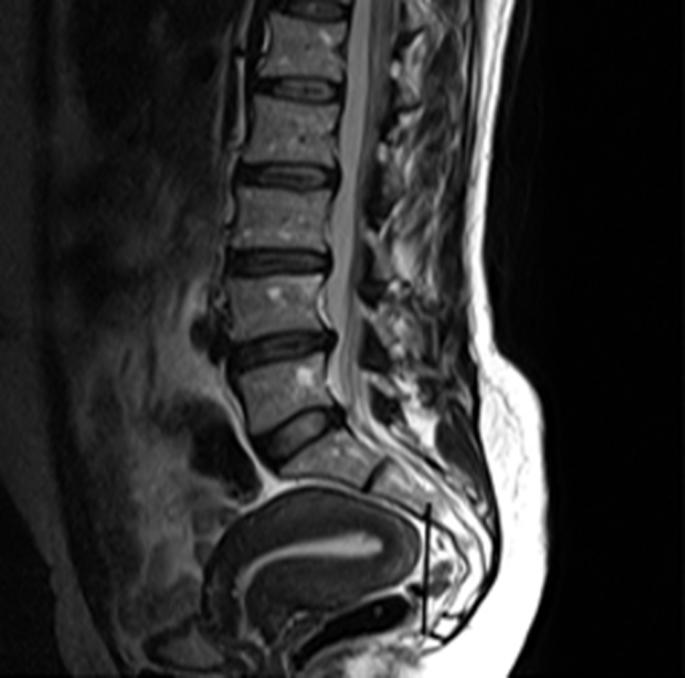

腰椎间盘磁共振成像期间腰椎的偶然椎体外发现。

Incidental extraspinal findings in the lumbar spine during magnetic resonance imaging of intervertebral discs.

To calculate the frequencies of incidental extraspinal findings and incidentally detected congenital anomalies or anatomical differences in the lumbar spine on magnetic resonance imaging (MRI) scans of intervertebral discs.

Of the 379(100%) patients, 90(23.7%) patients were presented with incidental findings. Among the incidental findings, 39(10.3%) were renal cysts, 10(2.6%) were retroverted uteri, 5(1.3%) were Nabothian cysts, 4(1.1%) were ovarian cysts, 10(2.6%) were uterine fibroids, 3(0.8%) were endometrial thickening, 11(2.9%) were indicative of hydronephrosis, 4(1.1%) were uncovered prostatic enlargement, 2(0.5%) were atrophic kidney, and 1(0.3%) each was of an ectopic kidney and bladder wall thickening, respectively.

计算在椎间盘磁共振成像(MRI)扫描中偶然发现的脊柱外异常以及偶然检测到的腰椎先天性异常或解剖差异的发生率。

379例(100%)患者中,90例(23.7%)有偶然发现。在这些偶然发现中,肾囊肿39例(10.3%),子宫后倾10例(2.6%),宫颈纳氏囊肿5例(1.3%),卵巢囊肿4例(1.1%),子宫肌瘤10例(2.6%),子宫内膜增厚3例(0.8%),肾积水11例(2.9%),前列腺增生4例(1.1%),肾萎缩2例(0.5%),异位肾和膀胱壁增厚各1例(0.3%)。